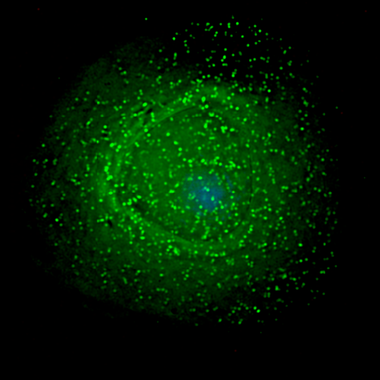

Visualizan las metástasis del melanoma antes de que ocurran e identifican nuevas dianas para su tratamiento